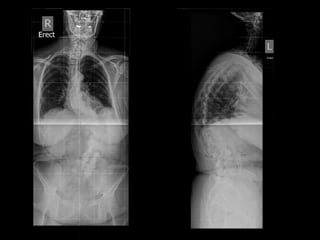

Not  all  spine  surgery  is  the  same…

DISCECTOMY FOR DISCHERNIATION Outcome •  Day  Surgery  procedure   •  back  to  sedentary  duHes  in  3  weeks   •  back  to  sport  in  6  weeks   •  good  or  excellent  result  in  90-­‐95%